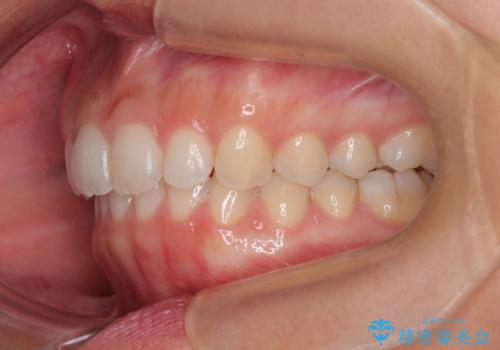

- 上の前歯が前方に飛び出していることを気にして来院された患者様です。

奥歯の咬み合わせをチェックすると、上顎歯列が相対的に前方に位置しているため、補助装置を用いて上顎歯列を確実に後方に移動させ、インビザラインで歯列を整えて行くこととしました。